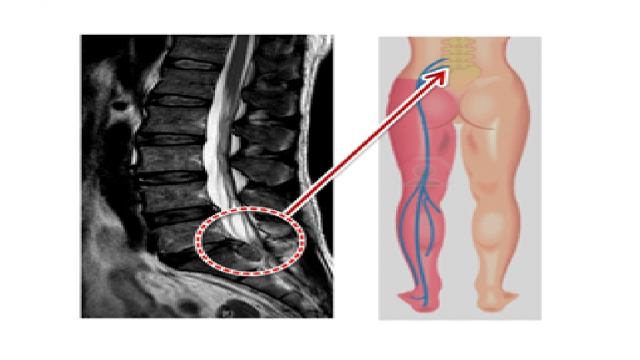

두 번째 증상으로는 다리로 방사되는 통증, 즉 방사통이 있습니다.

허리에서 시작된 통증이 엉덩이와 다리로 퍼지는 경우가 많으며, 이는 디스크가 신경을 압박하기 때문입니다.

이 경우는 주로 다리와 발에 무감각이나 따끔거림을 느끼며, 이는 신경 손상으로 인한 현상입니다.

허리디스크로 인해 일부 신경이 손상되면, 다리의 근력이 약해져서 걷기나 일상적인 활동이 어려워질 수 있습니다.